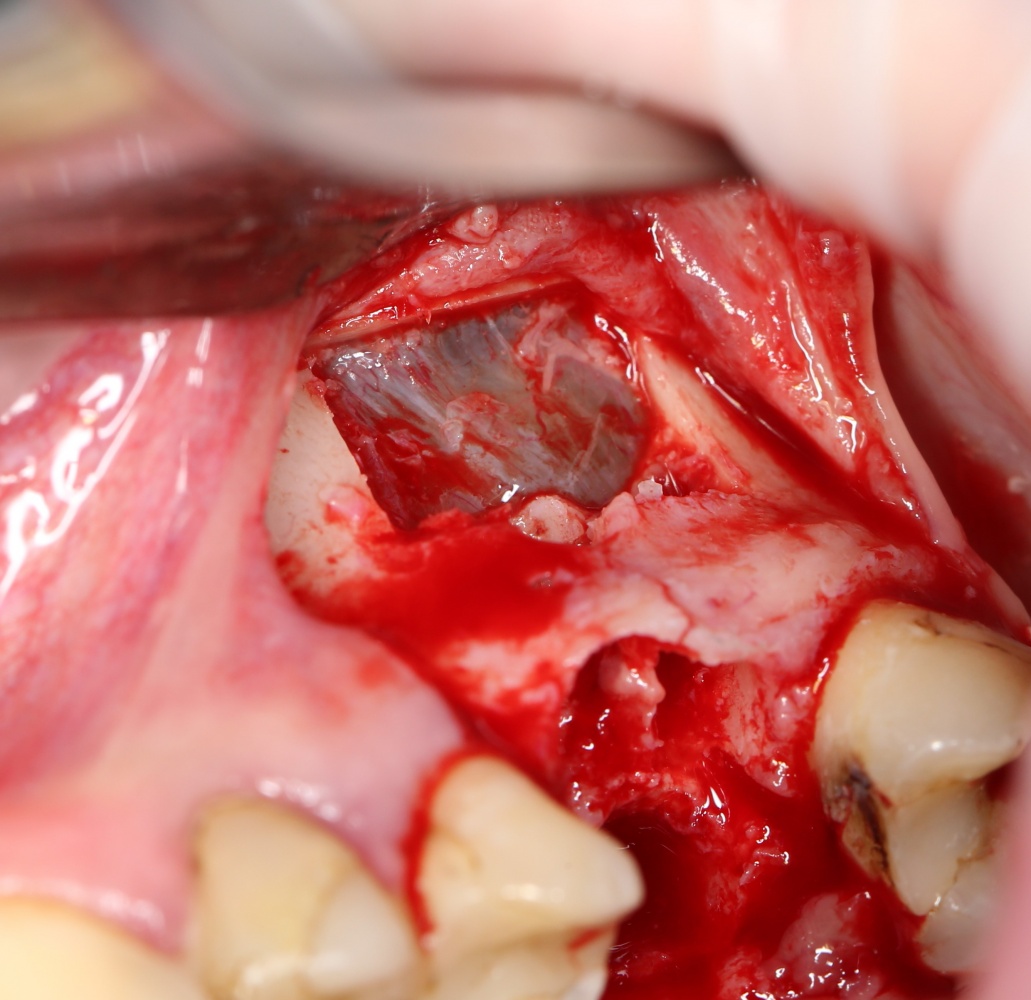

Синуслифтинг: что делать при перфорации слизистой оболочки гайморовой пазухи?